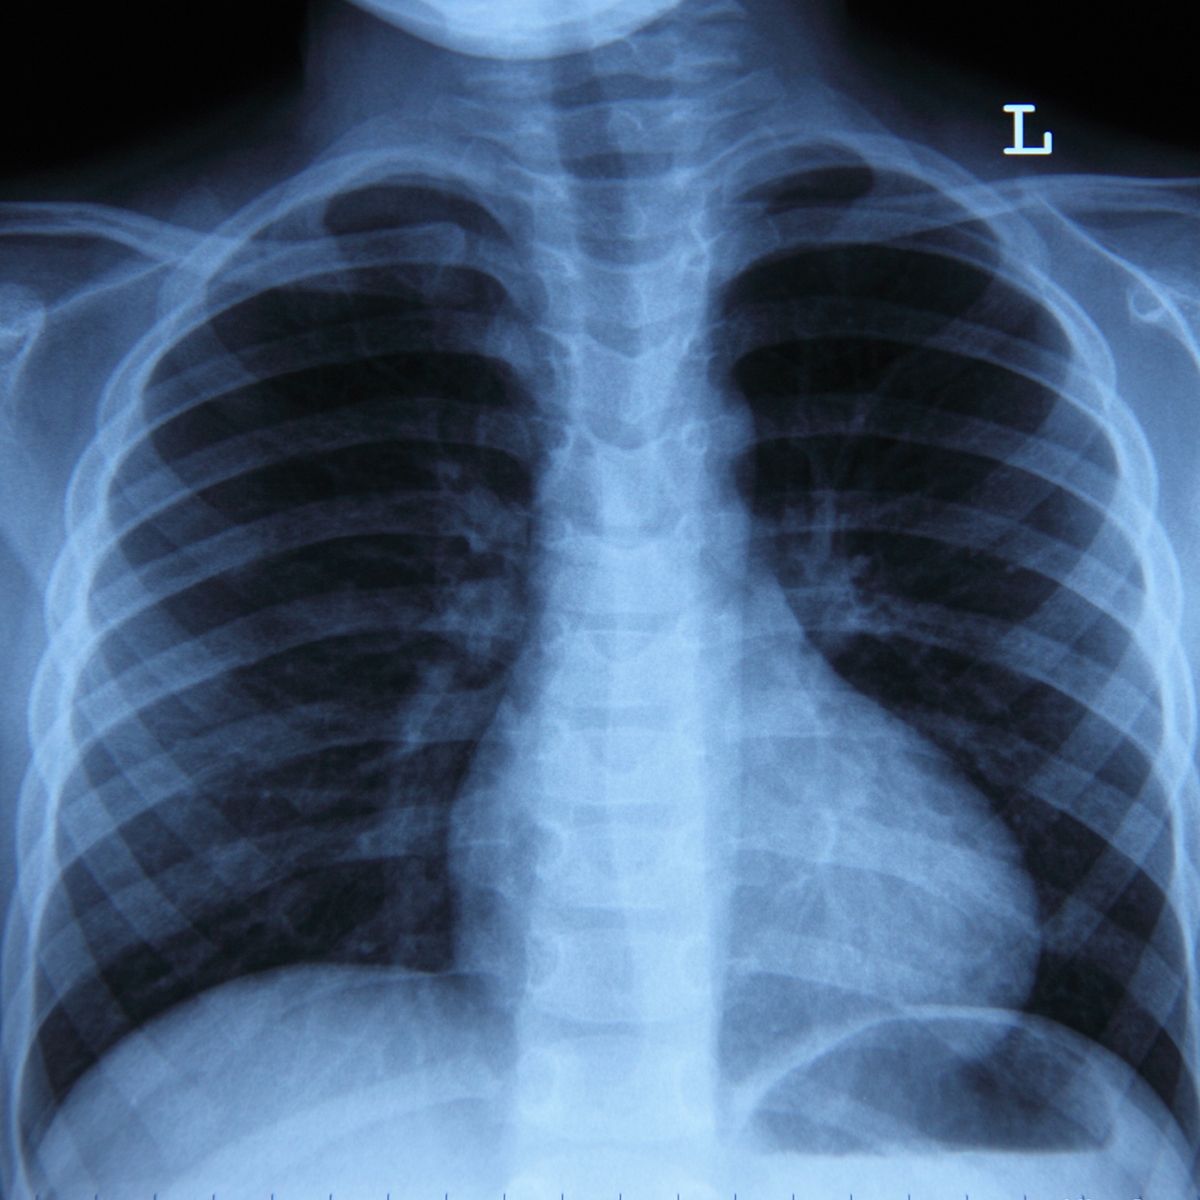

Some treatment-related cardiovascular events, such as atrial fibrillation, may be more common in patients with non-small cell lung cancer, research shows.

Patients with non-small cell lung cancer (NSCLC) may be at higher risk for treatment-related cardiovascular events, depending on their treatment type, according to a recent study from the journal Cancer.